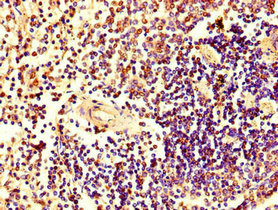

Immunohistochemistry of paraffin-embedded human spleen tissue using CSB-PA010726LA01HU at dilution of 1:100